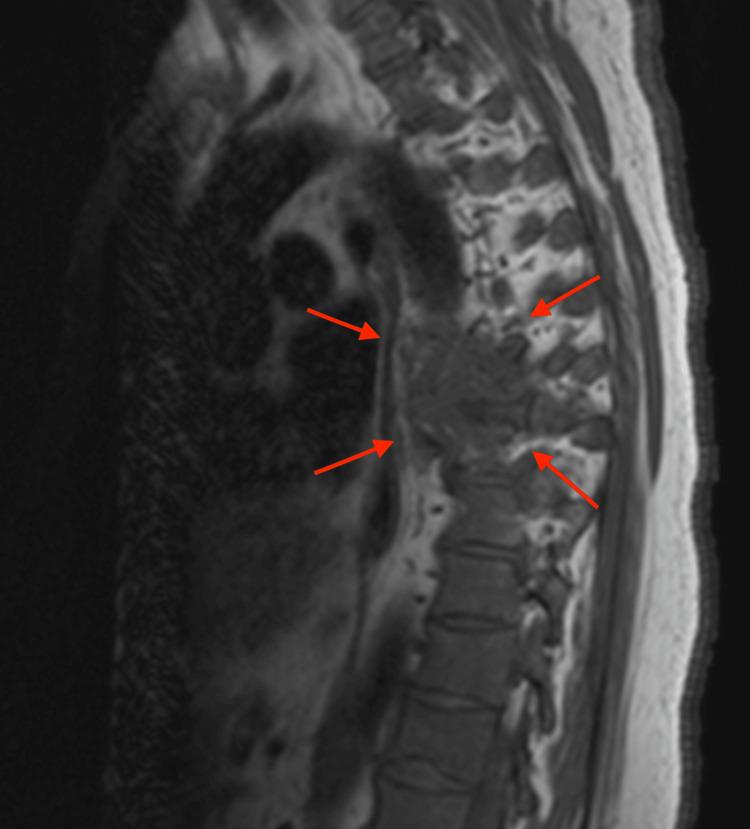

In this case report, we discuss the presentation, diagnosis, and management of a 67-year-old gentleman with stage II multiple myeloma with concurrent biopsy-proven bone plasmacytoma and why it is important to understand the molecular intricacies of these disorders. We emphasize the critical role of radiology in identifying, characterizing, and managing these lesions. Furthermore, we shed light on the critical differentiation between solitary extramedullary plasmacytoma and multiple myeloma and discuss treatment modalities for both conditions.

When Two Worlds Collide: A Rare Case of Multiple Myeloma With Extramedullary Plasmacytoma.